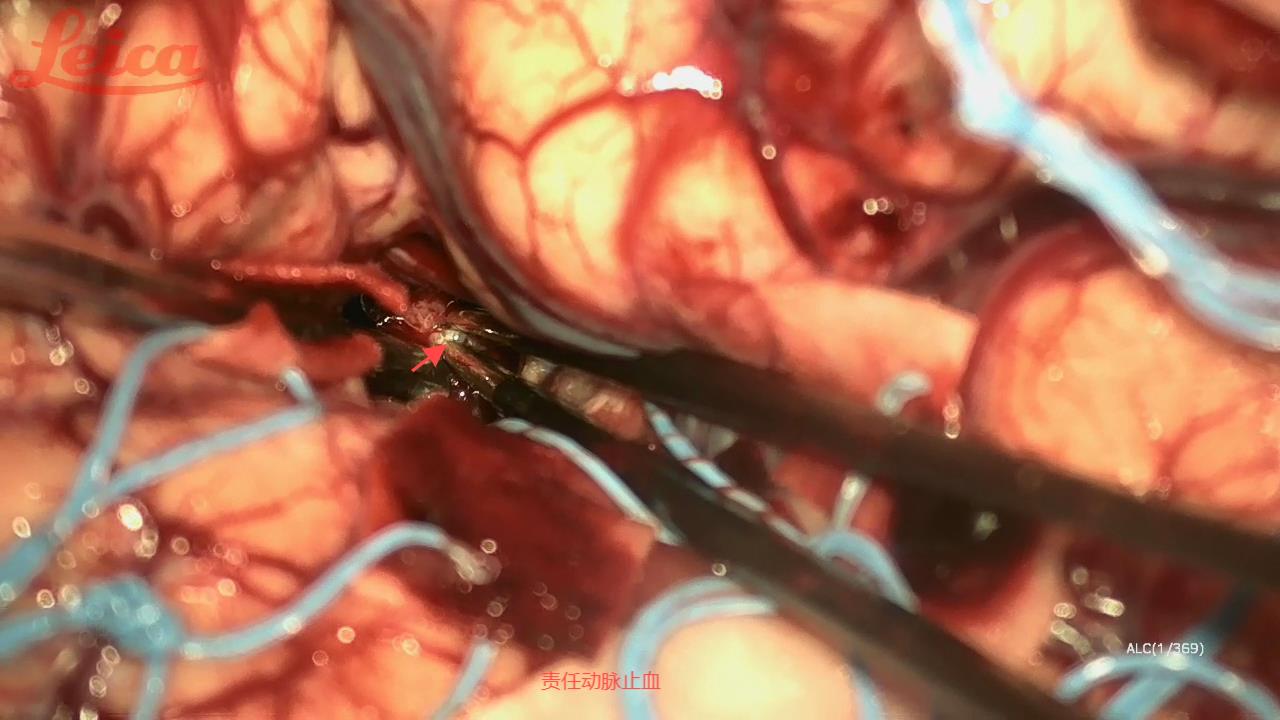

经外侧裂-岛叶造瘘清除血肿简要

经外侧裂-岛叶造瘘清除基底节出血